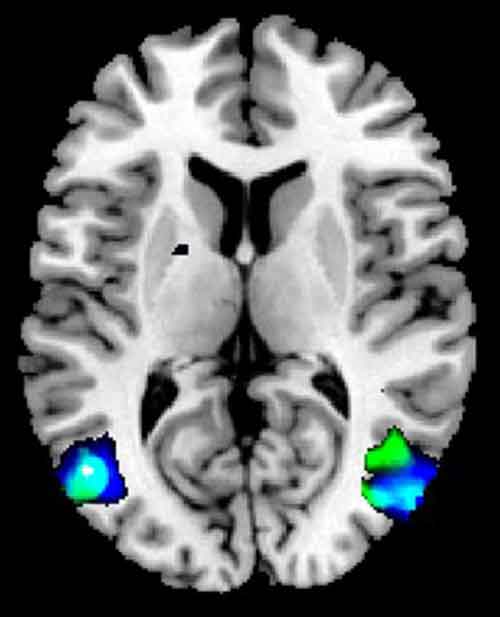

Meno materia grigia nelle aree del cervello coinvolte nella rappresentazione mentale di sé e nella manipolazione delle immagini. E’ questa carenza, stando a uno studio italiano pubblicato su ‘Psychiatry research: Neuroimaging’, a far sì che i malati alle prese con l’anoressia si vedano sempre grassi e fuori forma, anche se ormai il disturbo alimentare li ha ridotti pelle e ossa. La ricerca ‘made in Italy’ dimostra dunque, prove scientifiche alla mano, che c’è una base neurobiologica nella distorsione dell’immagine corporea, sintomo cardine dell’anoressia nervosa.

Per giungere a questo risultato, i ricercatori hanno confrontato la materia grigia di 16 adolescenti con anoressia, malati da meno di un anno, con quella di 16 teenager sani. Per farlo hanno utilizzato la risonanza magnetica e la nuova metodica di analisi della sostanza grigia nota, tra gli addetti ai lavori, come ‘Voxel Based Morphometry’. La scoperta dà un nuovo contributo alla comprensione dei meccanismi su cui poggia la malattia e apre la strada a nuove possibili strategie terapeutiche per metterla al tappeto.